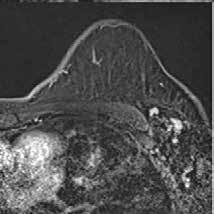

Se citó nuevamente en la consulta de Medicina Interna, apreciándose cierta mejoría subjetiva a nivel cognitivo, ganancia ponderal (64 kg) y difi cultades para la marcha. En la RMN solicitada meses después no se observó mejoría alguna, sino una progresión de la enfermedad con aparición de necrosis, atrofia y aumento de difusión en el esplenio del cuerpo calloso (Figura 4).

Figura 4. Resonancia magnética cerebral a los 8 meses. Secuencias T1, T2 y difusión, corte sangital y transversal. En el esplenio del cuerpo calloso se observa adelgazamiento, con presencia de un área de necrosis en las capas medias de hiperintesidad de señal periférica con aumento de difusividad. En comparación con RM previe se objetivan cambios evolutivos con necrosis, atrofia y aumento de la difusión. Hallazgos compatibles con la enfermedad de Maarchiafava-Bignami.